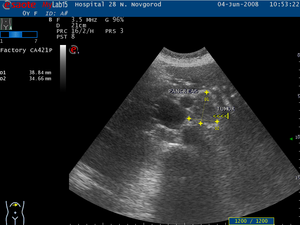

Тем не менее, даже такие незначительные симптомы могут полностью отсутствовать на ранних стадиях заболевания. Наиболее информативным методом для выявления болезни на самых ранних этапах остается ультразвуковое исследование органов пищеварения, а также компьютерная томография (КТ) или магнитно-резонансная томография (МРТ).